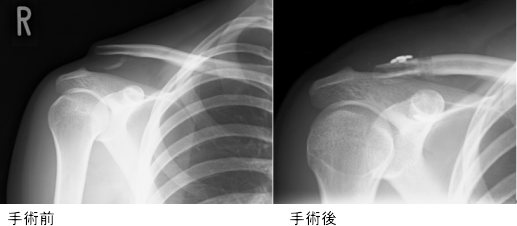

イラストの1は肩鎖関節脱臼をおこした関節をしめしています。陳旧性肩鎖関節脱臼では、脱臼をして経過がながいために、イラスト2のような急性期の肩鎖関節脱臼に対する手術をしても烏口鎖骨靭帯は治癒しません。肩鎖関節脱臼の手術が成功する(脱臼が整復され、痛みもなくなり、筋力も回復する)ためには烏口鎖骨靭帯が不可欠になります。陳旧性肩鎖関節脱臼では、烏口鎖骨靭帯のかわりに膝から採取した半腱様筋腱を烏口突起と鎖骨にとおし(イラスト3参照)、鎖骨にあけた穴をスクリューで固定します。この半腱様筋腱が烏口突起と鎖骨に癒合するまでは、肩鎖関節を整復するために金属ボタン2つと強い糸で固定をします。さらに長い半腱様筋腱を肩峰に固定します。(イラスト4参照)

脱臼整復が維持され、柔道に復帰した方もおられます。可動域の回復に時間がかかりますが、痛みが軽快し、患者さんは喜んでおられます。